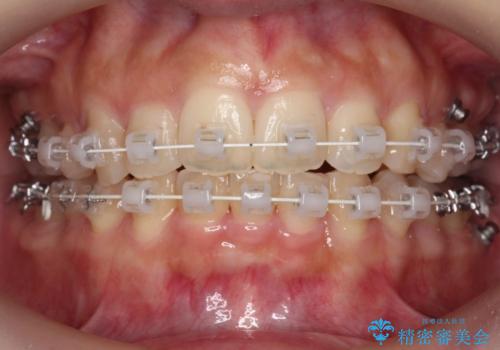

- 矯正装置

- ワイヤー矯正

- 出っ歯を主訴に来院。

上下のかみ合わせが1本分左右ともずれていました。

①上下左右合計4本抜歯(口元は一番下がるプラン、上の奥歯をさらに後ろに下げる必要があるため②より時間がかかる、上下正中は合う)

②上の歯を2本抜歯、下の歯は前歯1本と最小限の抜歯(矯正治療は早く終わる、口元は下がる、抜歯は3本、上下の正中は合わない)

を提示し、

②を選択されました。